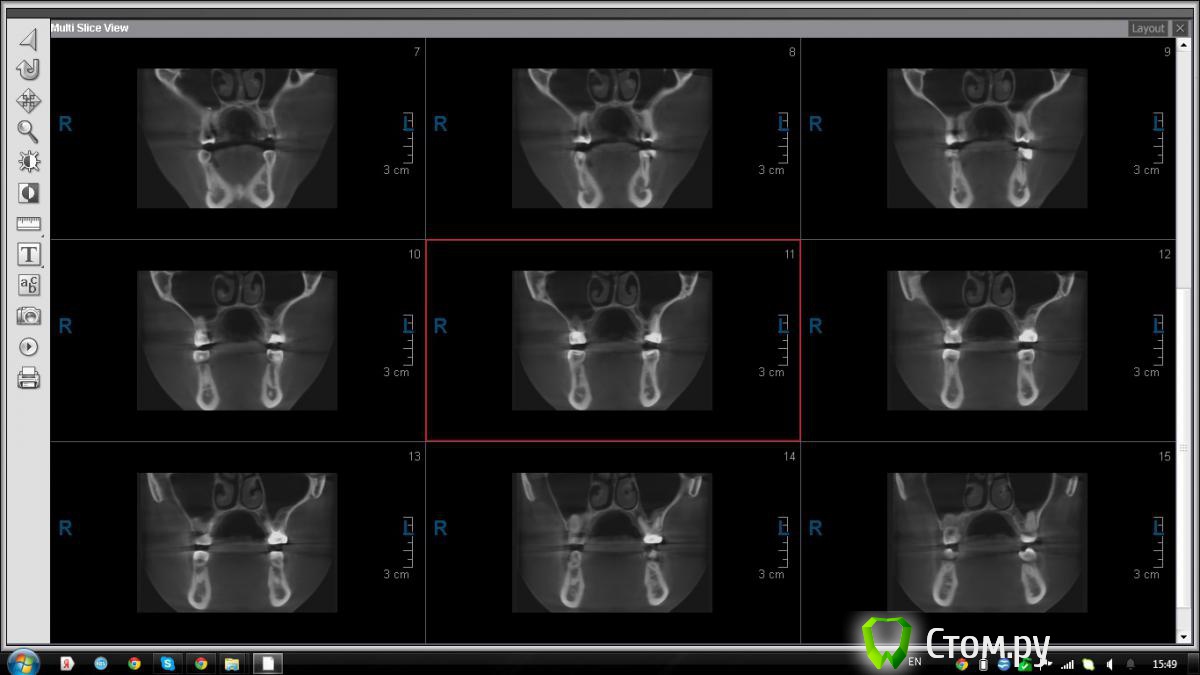

АнтонТЛТ Опубликовано 9 сентября, 2014 Поделиться Опубликовано 9 сентября, 2014 можно просто принт скрины Ссылка на комментарий

jm3300 Опубликовано 9 сентября, 2014 Автор Поделиться Опубликовано 9 сентября, 2014 вот, набросал Ссылка на комментарий

АнтонТЛТ Опубликовано 9 сентября, 2014 Поделиться Опубликовано 9 сентября, 2014 (изменено) это нижняя носовая раковина, возможно Изменено 9 сентября, 2014 пользователем АнтонТЛТ Ссылка на комментарий

АнтонТЛТ Опубликовано 9 сентября, 2014 Поделиться Опубликовано 9 сентября, 2014 я понял что это)))это артефакт от зуба, обратите внимание на правую сторону, там в пазухе тоже зуб есть, после эндодонтии)) Ссылка на комментарий